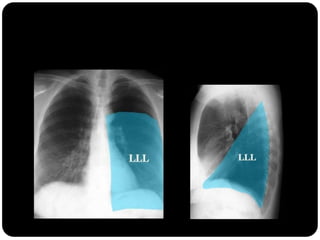

Atelectasia do lobo

inferior esquerdo

Atelectasias de lobos

inferiores deslocam

o hilo posterior e

medialmente;